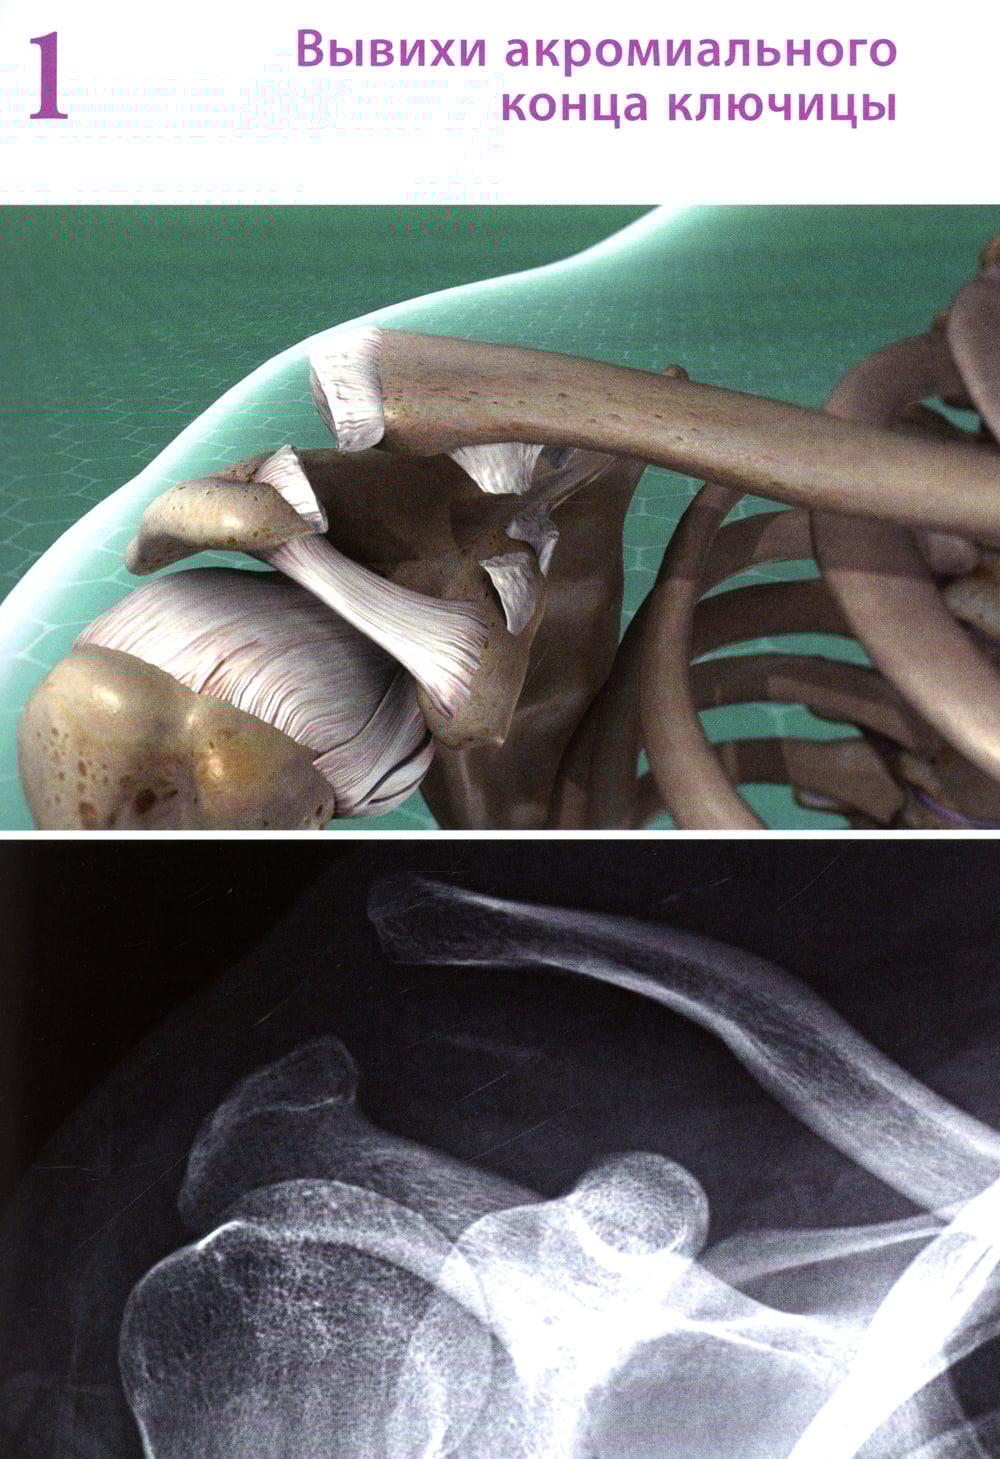

Аннотация: Повреждения ключицы: Учебное пособие

В учебном пособии представлена актуальная информация об особенностях диагностики и лечения повреждений ключицы. Главная задача книги - продемонстрировать широкий спектр решений проблемы переломов и вывихов ключицы. Авторы ставили перед собой цель обобщить обширную литературу и личный опыт в отношении выбора методов лечения повреждений ключицы. В основу положен опыт нескольких травматологических клиник, в которых авторы работали и работают многие годы. Для обучающихся в медицинских вузах по специальности «Травматология и ортопедия» студентов, клинических ординаторов, аспирантов, будет также полезно практикующим травматологам-ортопедам, спортивным врачам и реабилитологам.| Издательство | МИА |